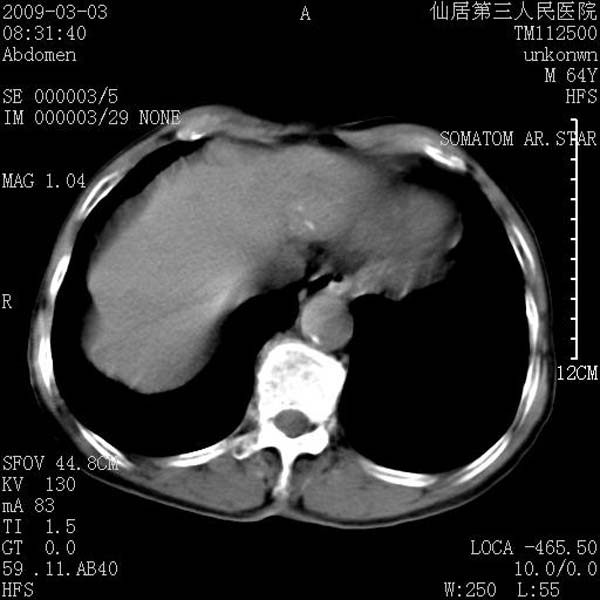

标题: CT18469:男性,64y,体检B超示肝脏低回声肿块,有胃溃疡手术 [打印本页]

标题: CT18469:男性,64y,体检B超示肝脏低回声肿块,有胃溃疡手术

患者,男性,64y,体检b超示肝脏低回声肿块,有胃溃疡手术史。